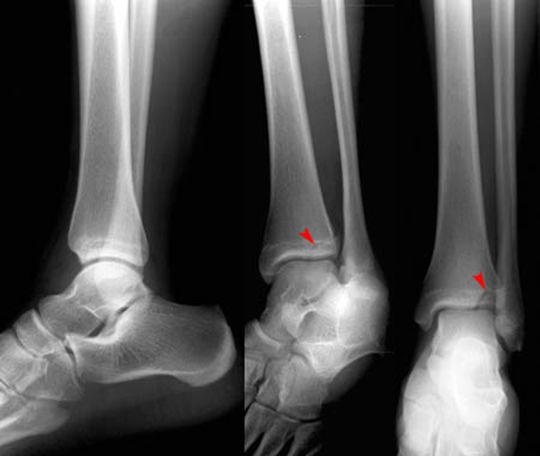

MaisonneuveFracture

• 腓骨中段骨折

• 下胫腓分离

正常踝关节

踝关节骨折

三踝骨折